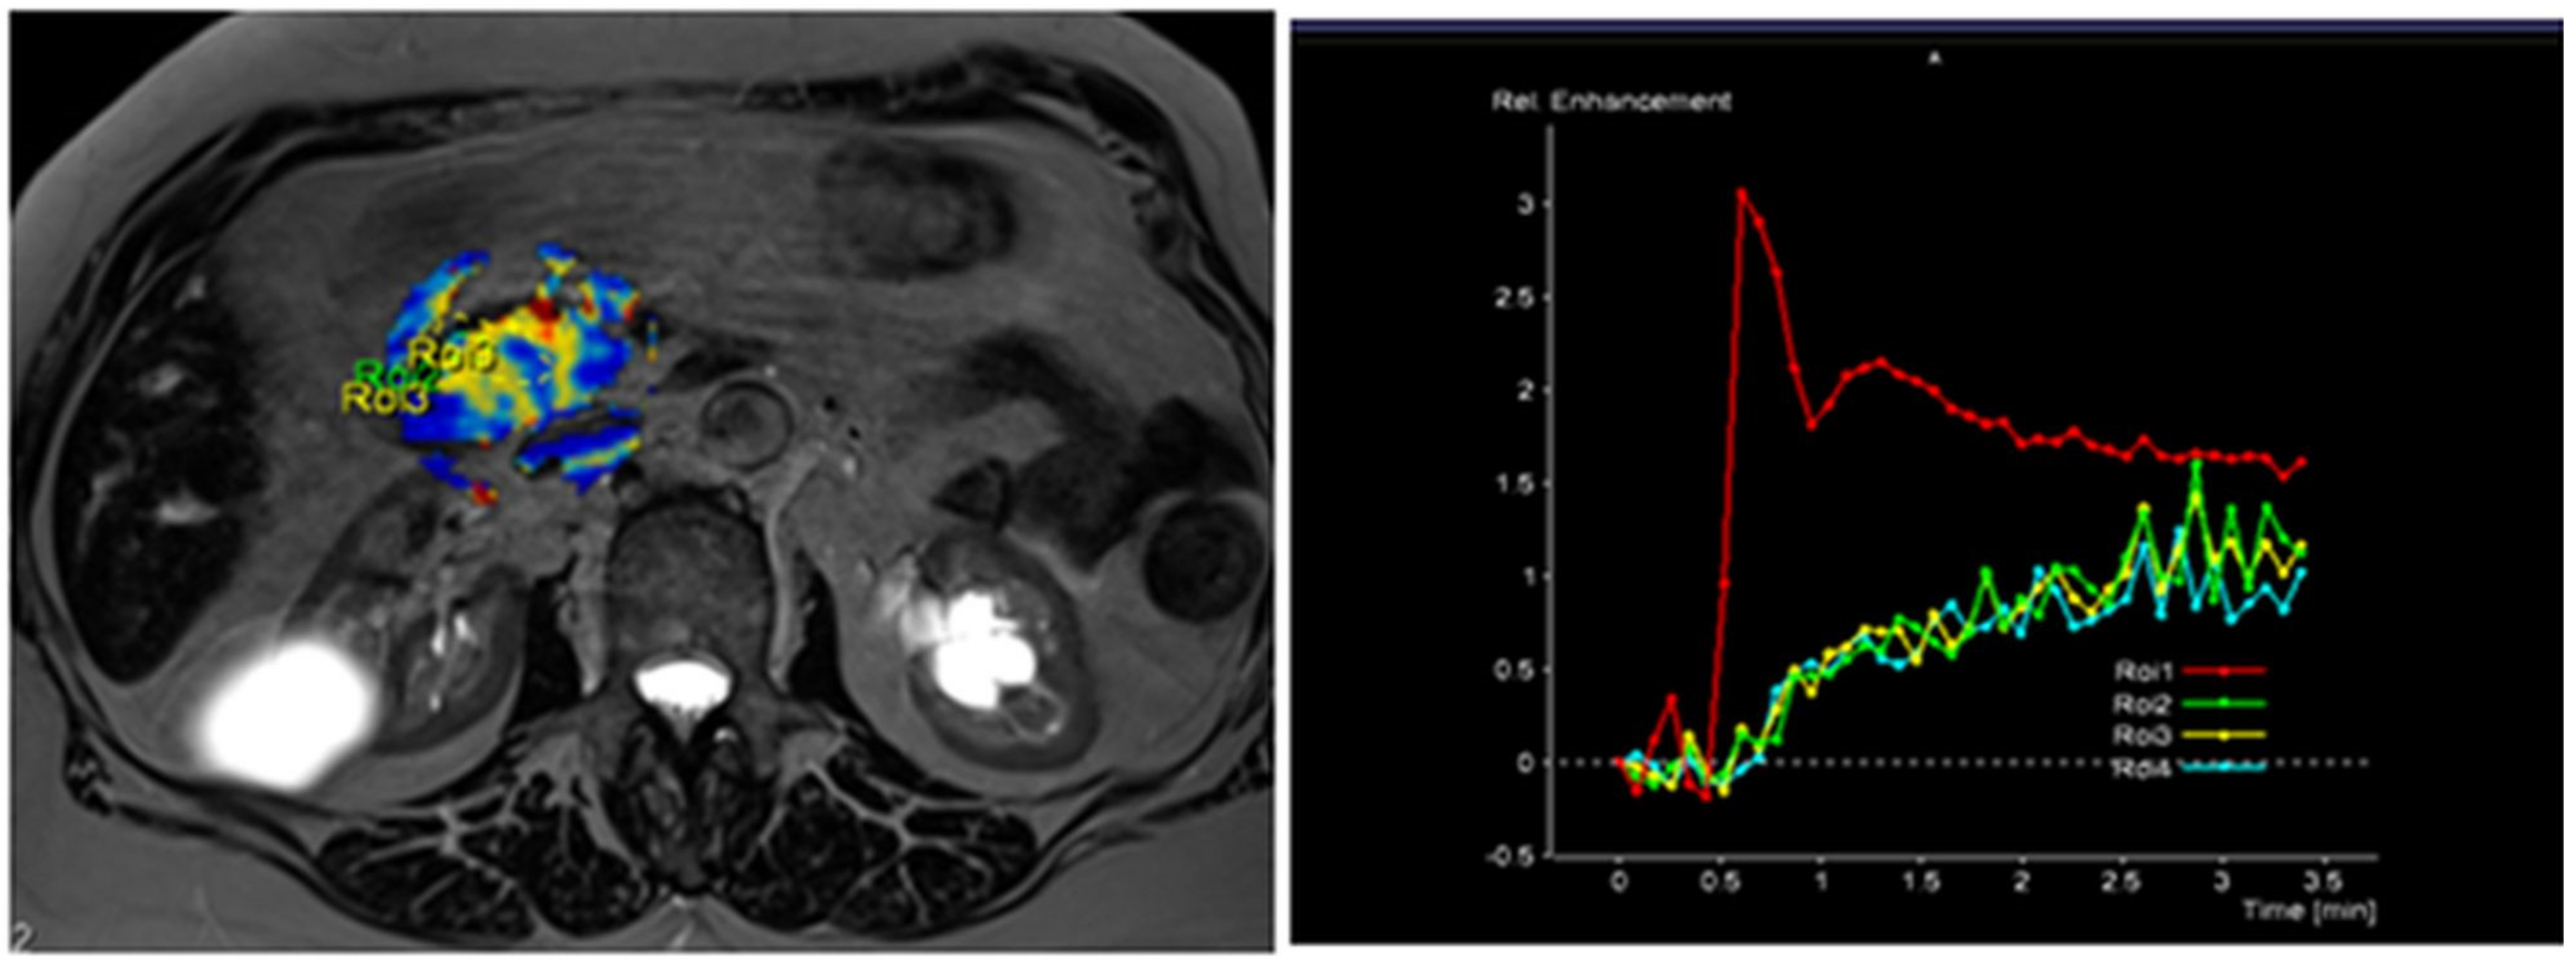

The radiological findings were compared with histopathological data. Histopathological analysis was performed at the Department of Pathological Anatomy, Lithuanian University of Health Sciences. The study patients were further grouped according to the differentiation grade (G value): well- and moderately differentiated (G1 + G2) and poorly differentiated (G3) PDAC. Images of DCE-MRI of non-tumorous pancreatic tissue and PDAC are presented in Figure 2 and Figure 3.

Figure 3. MRI perfusion images of G3 tumor in the head of the pancreas with TSIC—type II (slow enhancement and then continuous enhancement). The curve graph shows that pancreatic tumor enhances to a lesser extent than surrounding nontumoral pancreatic tissue. Most poorly differentiated (G3) tumors showed Type II pattern enhancement.